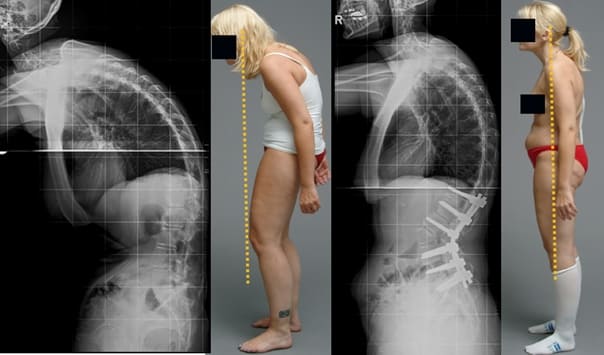

Mire estas fotografías. Esto es lo que les sucedió a todos los que ignoraron los síntomas. Hoy, estas personas están completamente sin esperanza, y muchos de ellos no tienen a quién acudir en busca de ayuda. ¿Realmente, quiere un destino así?

Mujer de 52 años. Desplazamiento y deformación severa del disco intervertebral, compresión de los nervios y daño a la médula espinal.

"Joroba de viuda" — deformación de las vértebras y dolor crónico, insoportable, que se intensifica cada día.

Hernia de disco intervertebral, compresión de los nervios, pérdida de sensibilidad y parálisis parcial de las piernas.